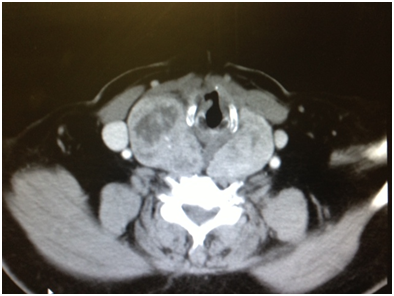

Figure 2 CT scan soft tissue neck showing right thyroid lobe enlargement at the level of hyoid bone, again displacing carotid artery.